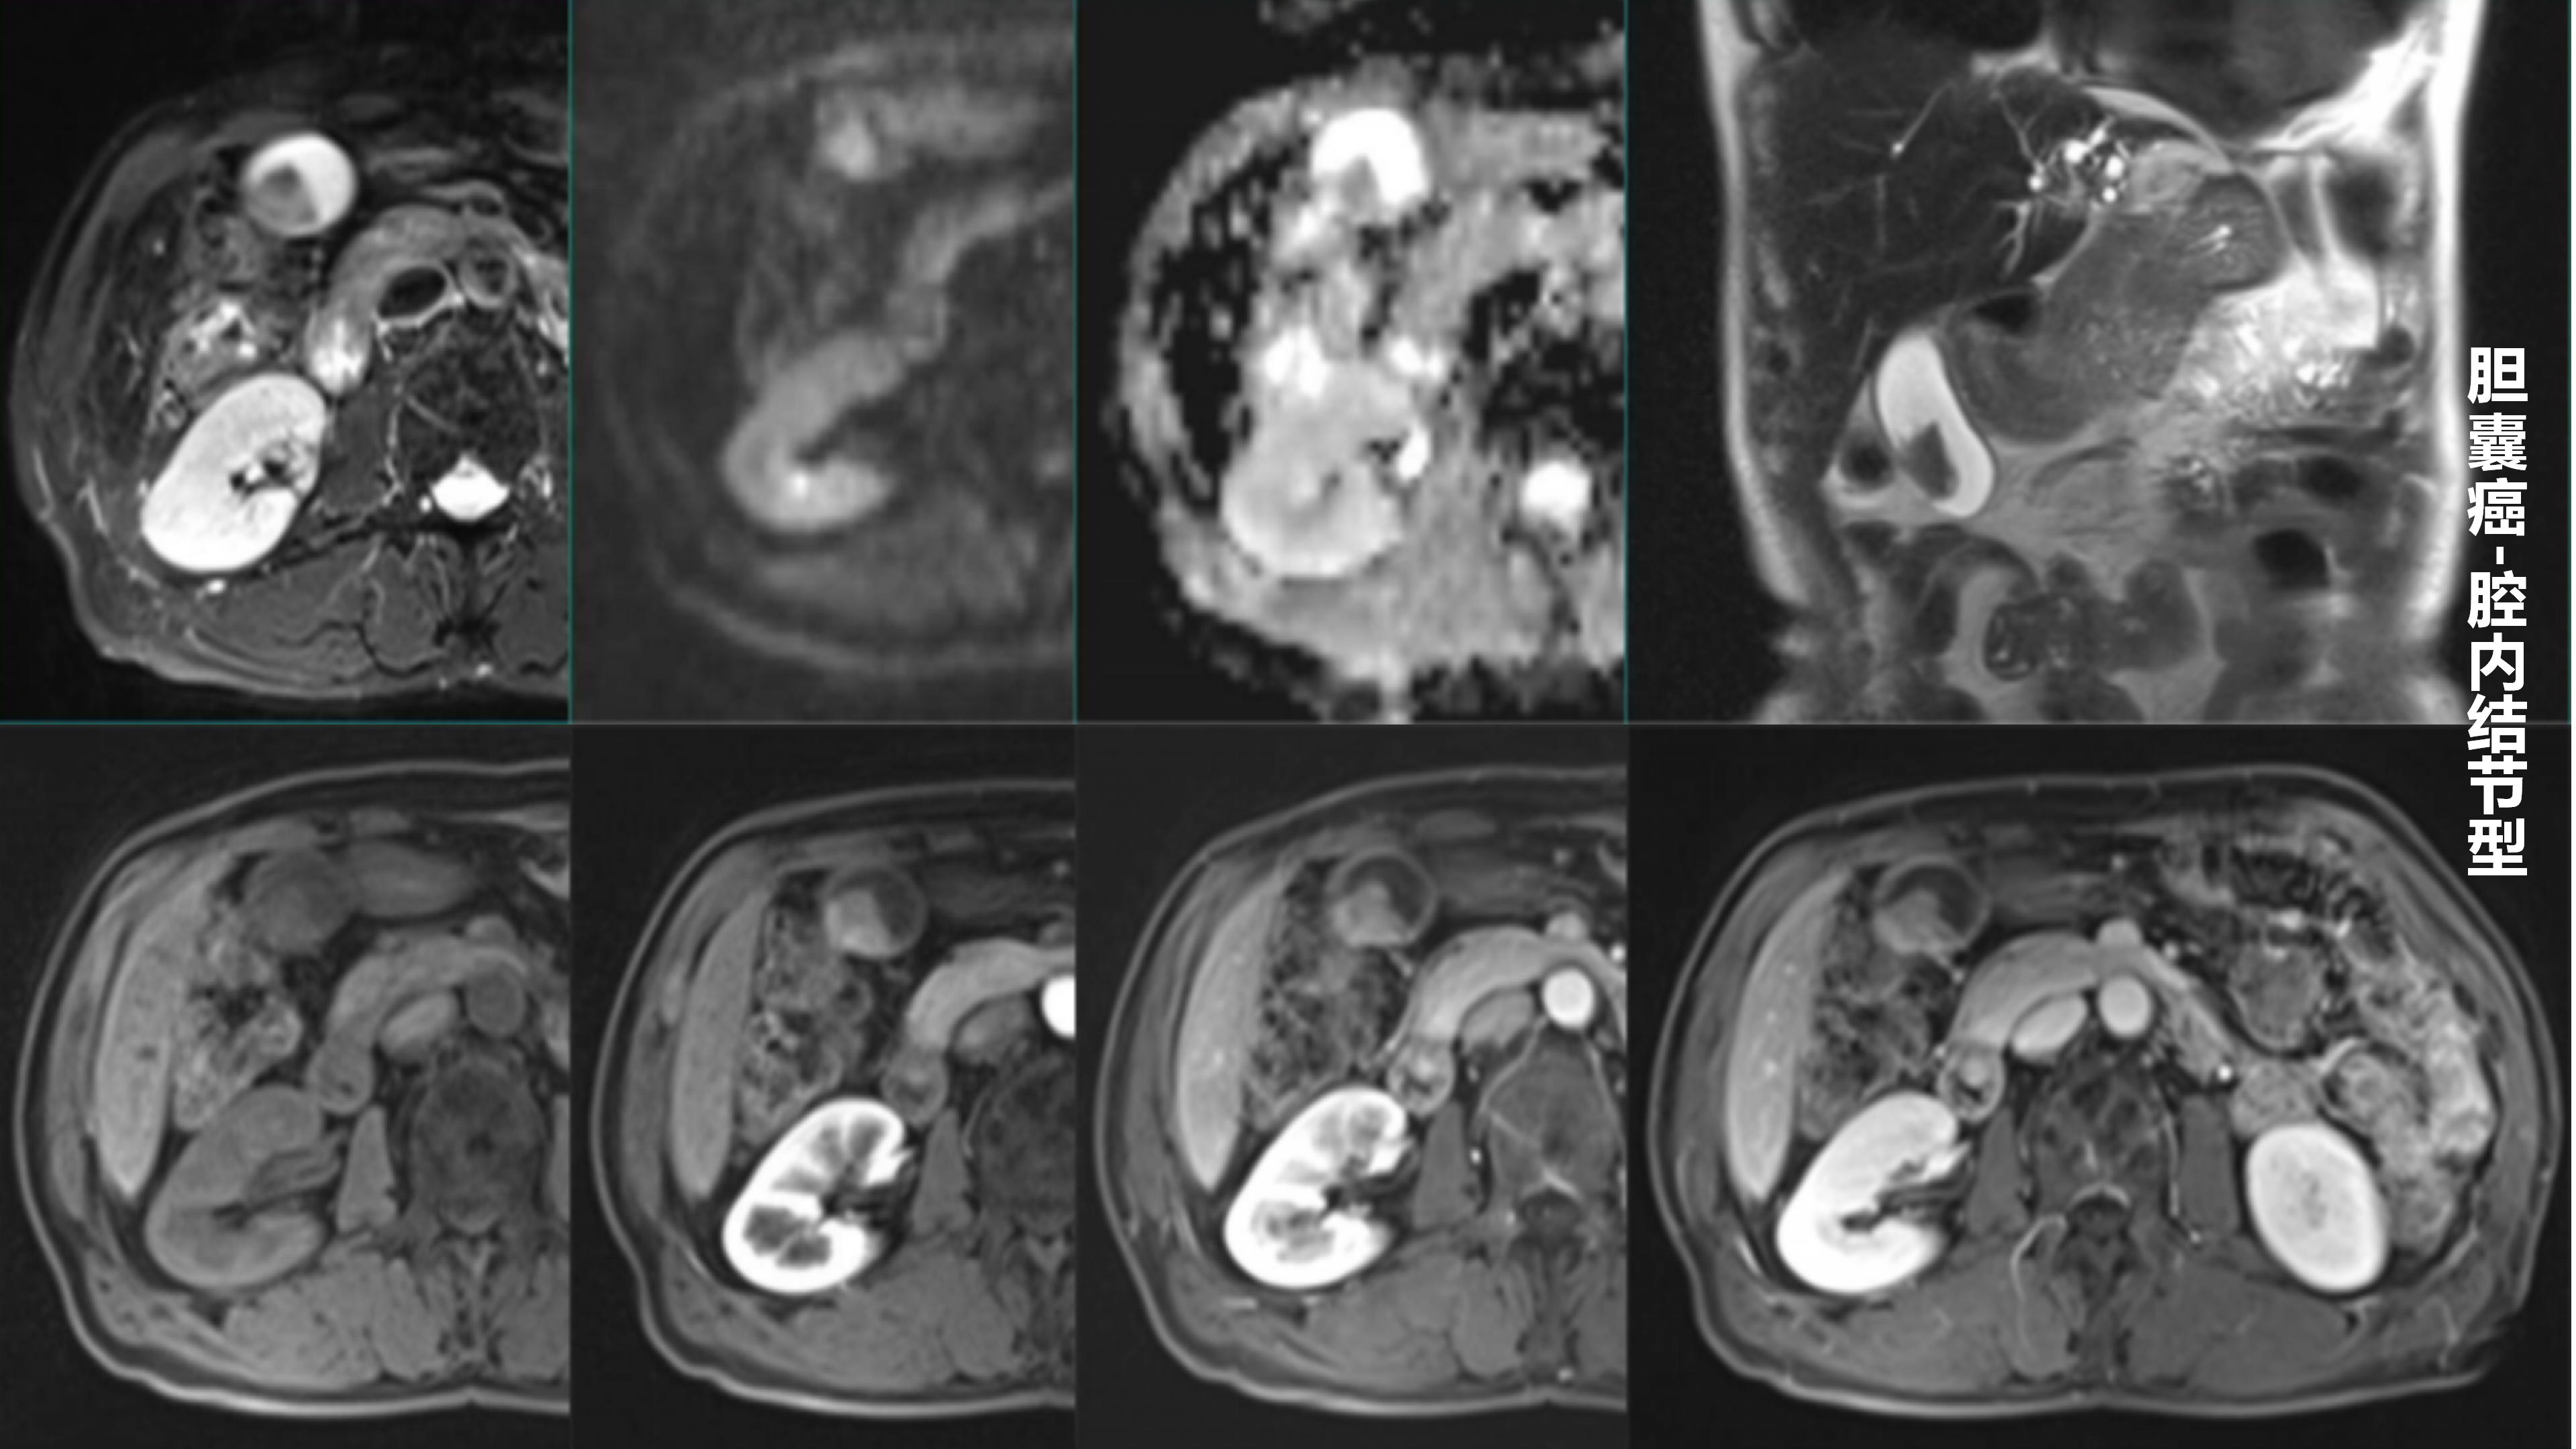

胆囊癌-鼎湖社群读片病例